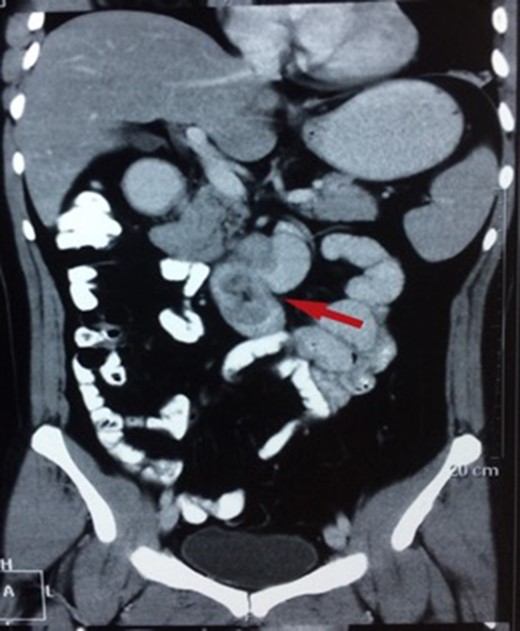

There were three males and one female who had Brunner’s gland hyperplasia as the pathological finding in their surgical specimens following operations for duodenal lesions. Their mean age at presentation was 39.7 ± 10.14 (range: 30–52) years and their presenting features were abdominal pain in two patients, vomiting (2), and upper gastrointestinal bleeding (2). The duration of their symptoms varied between 4 days and 4 years prior to presentation. All patients underwent an upper gastrointestinal endoscopy (Figs 1 and 2) and abdominal computed tomography(Figs 3 and 4) scans as part of their evaluation. The details of patient presentation, evaluation, surgical procedure and outcomes are described in Table 1.

CT (transverse) image showing first and second part of duodenum filled with a mass lesion.

| Case 1 | 30/M | 3 months | Vomiting, Malena | Well defined rounded hypodense submucosal lesion in second part of duodenum (Fig. 1) | Smooth mucosal bulge likely due to submucosal lesion in D2 with difficulty in negotiating scope beyond (Figs 2 and 3) | Normal duodenal mucosal fragments with mild lympho-mono nuclear cell infiltrate in the lamina propria | Pancreaticoduodenectomy | 2 | 2 days | 6 |

These lesions are often difficult to differentiate from other submucosal lesions in this location pre-operatively from gastrointestinal stromal and neuroendocrine tumours. Large adenomas can be detected by ultrasonography and computed tomography [8]. CT is also useful to confirm the absence of extra-luminal extension of a Brunner’s gland adenoma [9]. In our series, all patients were symptomatic at presentation and were being evaluated for these, and lesions found incidentally (e.g. after pancreaticoduodenectomy specimens for cancer) were excluded.